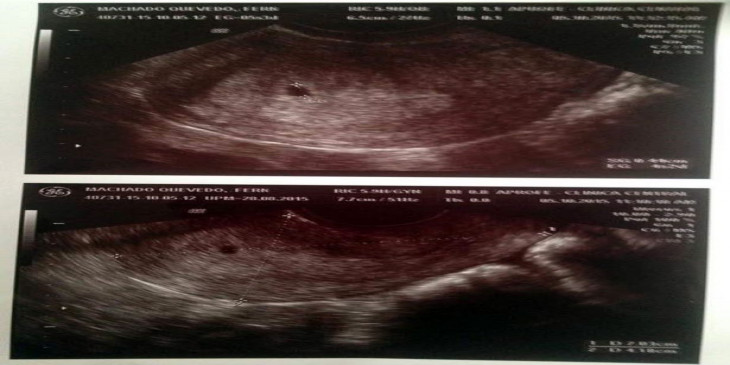

ဖာနန္ဒိုမာရွာဒိုကေတာ့ ဗင္နီဇြဲလားႏိုင္ငံကျဖစ္ၿပီး ခုခ်ိန္မွာ ကိုယ္၀န္ ၃ လ လြယ္ထားရၿပီလို႔ ဆိုပါတယ္။

ဓာတ္ပုံ - CEN